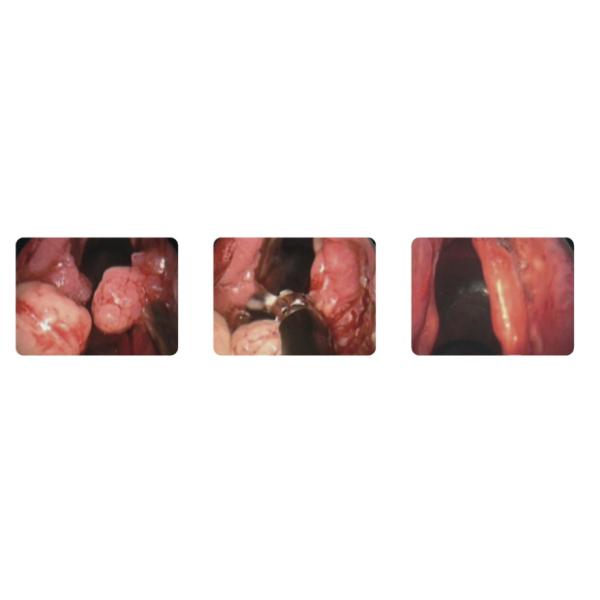

Поставляется с функциями и аксессуарами для всасывания и резекции, хорош для CAUP, UPPP, тонзилектомии, аденоидектомии, папилломы, полипуса и других опухолевых операций.

Он поставляется с функцией и аксессуарами для безопасной и эффективной хирургии пораженных тканей в скрытых и глубоких местах, например, глубокой горла и жесткой основы.